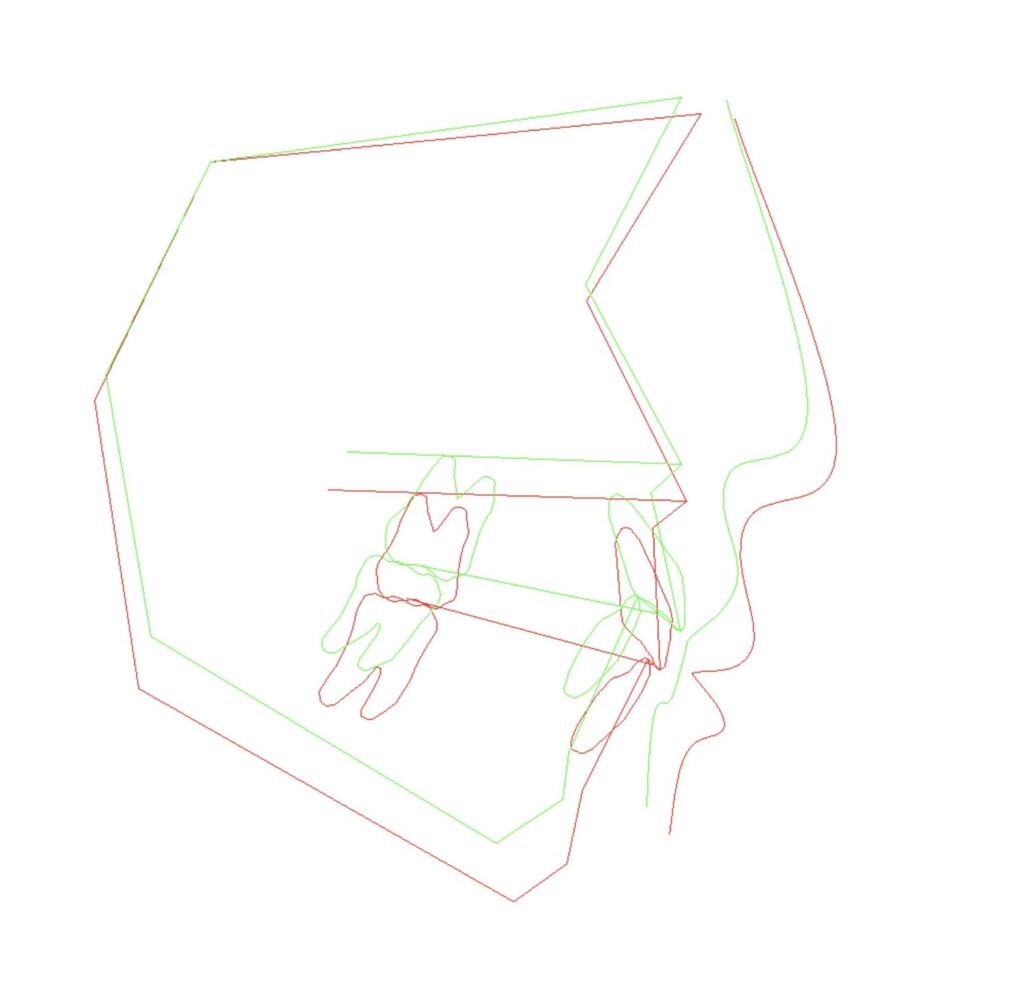

検査結果の説明

アクティビティーの終わりには検査を行い、親御さんとお子さんと一緒に変化を見ています。

悪い癖が改善しいい癖に変わることで、歯並びだけでなく顔もより良く成長していきます。

緑から赤へ変化しています。

よりいいお顔立ちになりました。